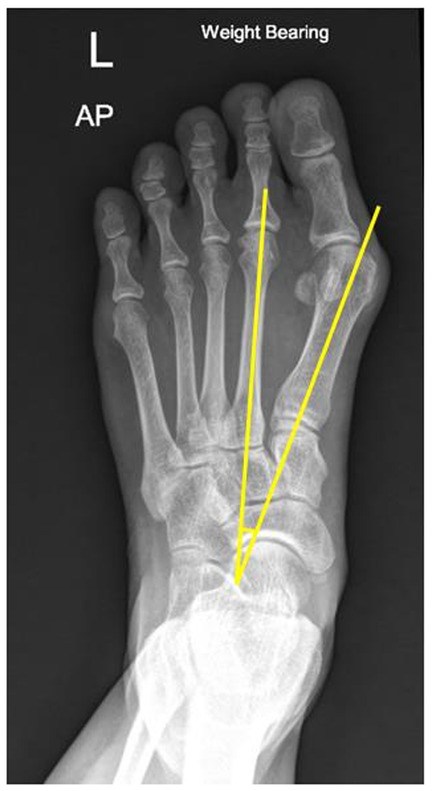

1. 1,2 Intermetatarsal angle (IMA): The centres of the proximal and distal metaphyseal–diaphyseal areas of 1st and 2nd metatarsal bones were marked as the axis of each bone. The intersection of the 1st and 2nd metatarsal axes was defined as the IMA. An IMA of less than 9 degrees was considered normal (4) (Figure 1).

Figure 1

X-ray image of a left foot in a weight-bearing position. Yellow lines are drawn along the midline of first and second metatarsal bone. Their intersection indicates angle measurement.

Figure 1. Illustration of IMA measurement in the weight-bearing plain film; the centres of the proximal and distal metaphyseal–diaphyseal areas of the 1st and 2nd metatarsal bones were marked as the axis of each bone. The intersection of the 1st and 2nd metatarsal axes was defined as the 1,2 intermetatarsal angle.